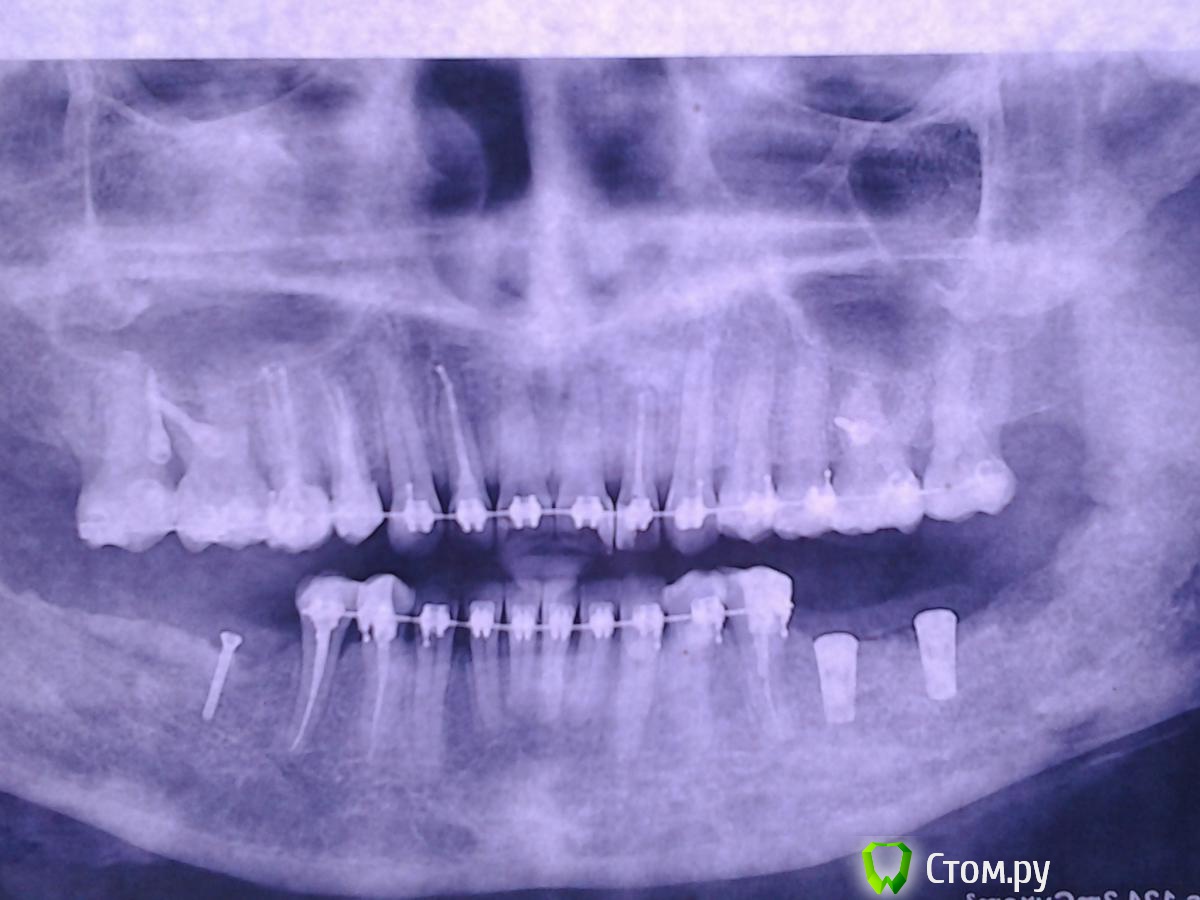

Nyurok Опубликовано 15 июня, 2014 Поделиться Опубликовано 15 июня, 2014 Здравствуйте, уважаемые врачи. С профессиональным вас праздником!Ситуация. 2 месяца назад операция "костная пластика" аутотрансплантатом. Всё хорошо, никаких субъективных ощущений. Через 1.5 месяца после операции возник сильный отек, и онемение левой половины нижней губы и левой части подбородка и практически одновременно с этим на другой стороне сделали операцию - 2 импланта и костная пластика, тоже своей костью. Принимала лекарства - кетонал, цефтриаксон, диазолин. Отек слева почти прошел, оставалась небольшая припухлость снаружи, но во рту отёк сохранялся и к тому, что было через 1 - 1.5 после операции не пришло. Справа, где импланты небольшая постоянная тупая боль. Через 2 недели от возникновения отёка (через 2 месяца после операции) в углу слева, где брали кость - открылся свищ, без заметного отделяемого, отек и онемение сохраняются. Пару дней назад справа и слева, мест забора кости, удалили некротизированные костные ткани (во время операций туда клали гемостатические губки), слева ещё удалили 1 винт из костного блока и отшлифовали верхний слой блока, зашили , место где блок. Лекарства - абактал, кетонал, диазолин.Сейчас. Справа ощущения значительно улучшились. Слева - улучшений нет. Отек, онемение, тяжесть всей левой челюсти до уха и где подчелюстные узлы.Прошу вас сказать, что есть сейчас на снимках и что делать.Состояние, как мне кажется, критическое. Надеюсь на помощь. Ссылка на комментарий

Nyurok Опубликовано 15 июня, 2014 Автор Поделиться Опубликовано 15 июня, 2014 ничего не понял, вы что снимки перевернули?Я ориентировалась где у меня право, там и снимок правой стороны. Как точно нужно - не знаю. Импланты это правая сторона, винтик левая Ссылка на комментарий

Nyurok Опубликовано 15 июня, 2014 Автор Поделиться Опубликовано 15 июня, 2014 какая зона вас смущает? обведите кружочкомизвините, не знаю как это сделать. Вся практически левая сторона нижней челюсти отличается от правой, она темнее, т.е. получается это разрежение кости? Вниз от винтика, 4-ки 5-ки до края нижней челюсти. Ведь у меня после вчерашней манипуляции нет улучшения? Значит источник инфицирования не устранен? Ссылка на комментарий

Bier Опубликовано 15 июня, 2014 Поделиться Опубликовано 15 июня, 2014 http://forum.stom.ru/topic/1640-snimok-zubov/особых проблем я не вижу на снимке. Ссылка на комментарий